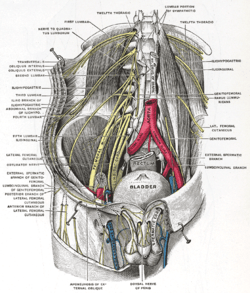

Deep and superficial dissection of the lumbar plexus. (Same note as above.)